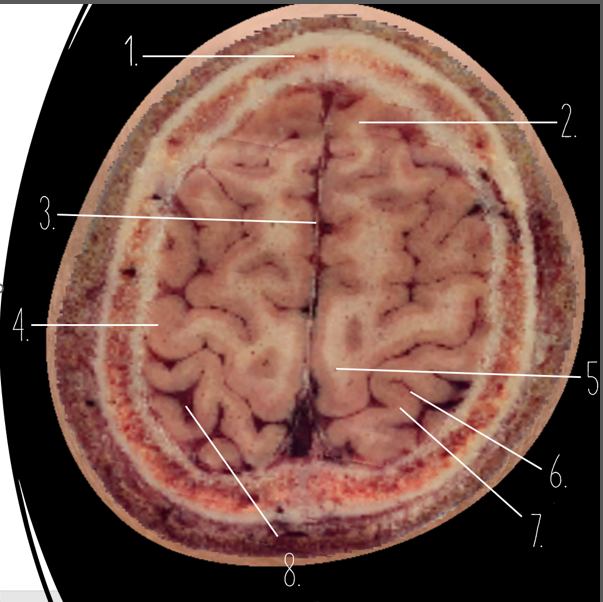

1

Frontal Bone

2

Frontal Lobe

3?

Falx Cerebri

4?

Gray Matter

5?

White Matter

6?

Sulcus

7?

Gyrus

8?

Fissure